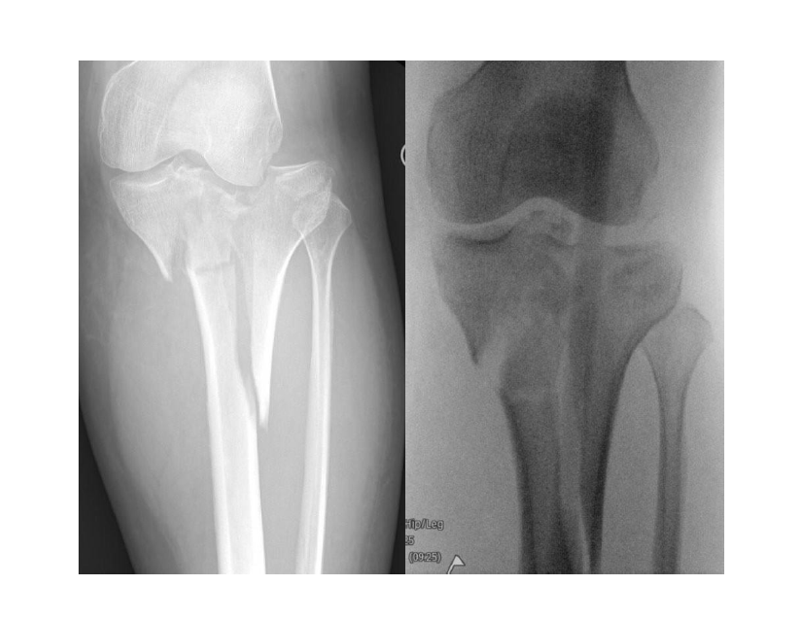

A 40-year-old female sustained a displaced tibial plateau fracture (fig.1) with marked soft-tissue swelling, tibia offset and joint depression, conferring ~50% ACS risk.